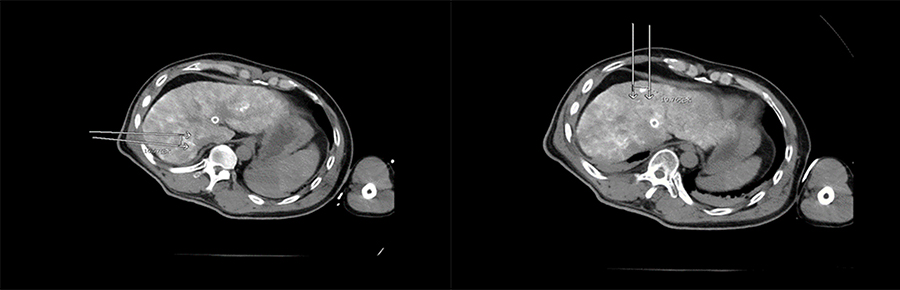

▲ 患者一手术过程

▲ 患者二手术过程